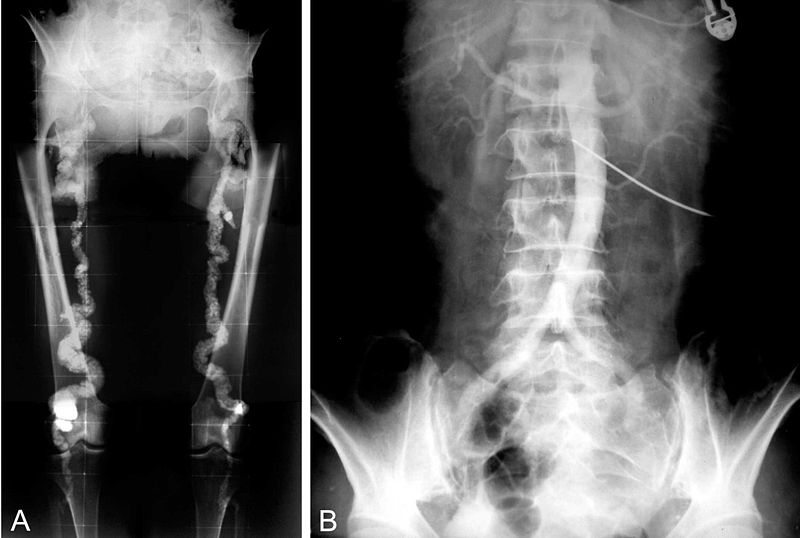

Mönckeberg Medial Calcific Sclerosis

Mönckeberg medial calcific sclerosis results in the calcification of the muscular tunica media portion of medium-sized arteries.

Mönckeberg medial calcific sclerosis is non-obstructive.

Mönckeberg medial calcific sclerosis is typically not clinically significantly.

Mönckeberg medial calcific sclerosis is usually an unintended discovery in X-ray mammography.